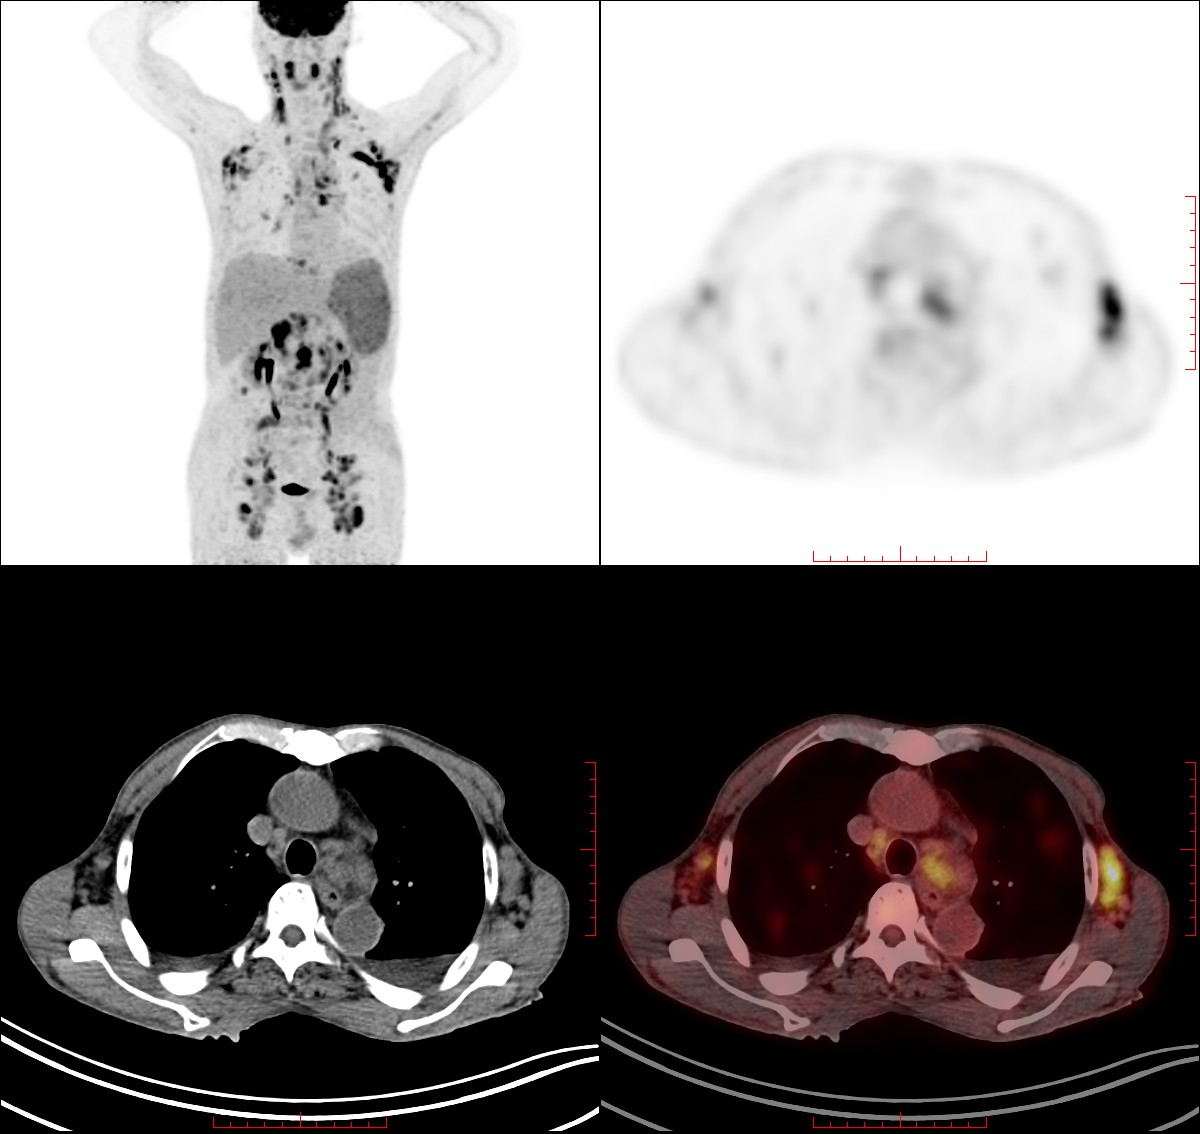

海南医院立足于服务海岛官兵及百姓医疗保障服务,从第一台PET/CT(西门子Biography 64 PET/CT)及医用回旋加速器(住友HM-10L)起,陆续引进包括ECT Brightview XCT,卧式运动踏车(德国ergosana)……在内多项设备,其中PET/CT是一种反映病变的基因、分子、代谢和功能状态的成像设备。它通过病灶对显像剂的摄取,经计算机后处理反映其代谢变化,从而为临床提供有价值的疾病生物的代谢信息。PET/CT成像可以一次性获得全身情况,从而达到诊断疾病和早期发现病变的目的,具有灵敏、定位准确的特点,对于肿瘤的早期发现、鉴别和肿瘤分期有很好的临床指导意。